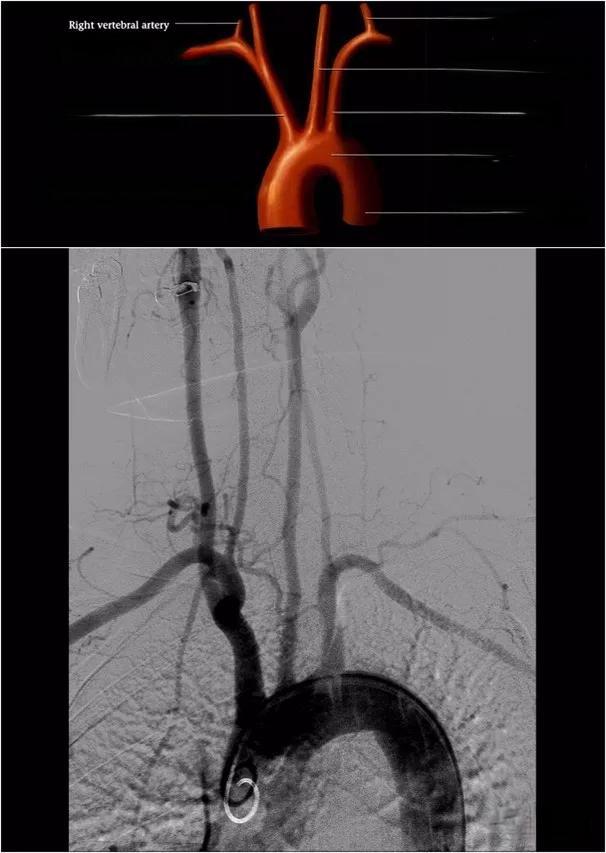

颈部及颅内动脉影像分段

颈内动脉(ICA)是颈部及颅内动脉的主要组成部分,通常被分为7个解剖段。C1段(颈段)起源于颈总动脉,终止于颈动脉管颅外口。C2段(岩段)位于颈动脉管内,C3段(破裂孔段)则位于破裂孔附近。C4段(海绵窦段)是ICA的主要部分,行走于海绵窦内。C5段(床突段)短而斜行,C6段(眼段)常发出重要分支如眼动脉。最后,C7段(交通段)发出后交通动脉和脉络膜前动脉。

影像学技术在颈部及颅内动脉的诊断中扮演着核心角色。数字减影血管造影(DSA)是评估这些血管的金标准,能够提供详细的血管解剖信息。然而,随着CT血管造影(CTA)和MRI血管造影(MRA)技术的发展,这些无创性检查方法在临床实践中也越来越受欢迎。它们不仅能够显示血管的形态,还能评估血流动力学变化,为临床决策提供全面的信息。